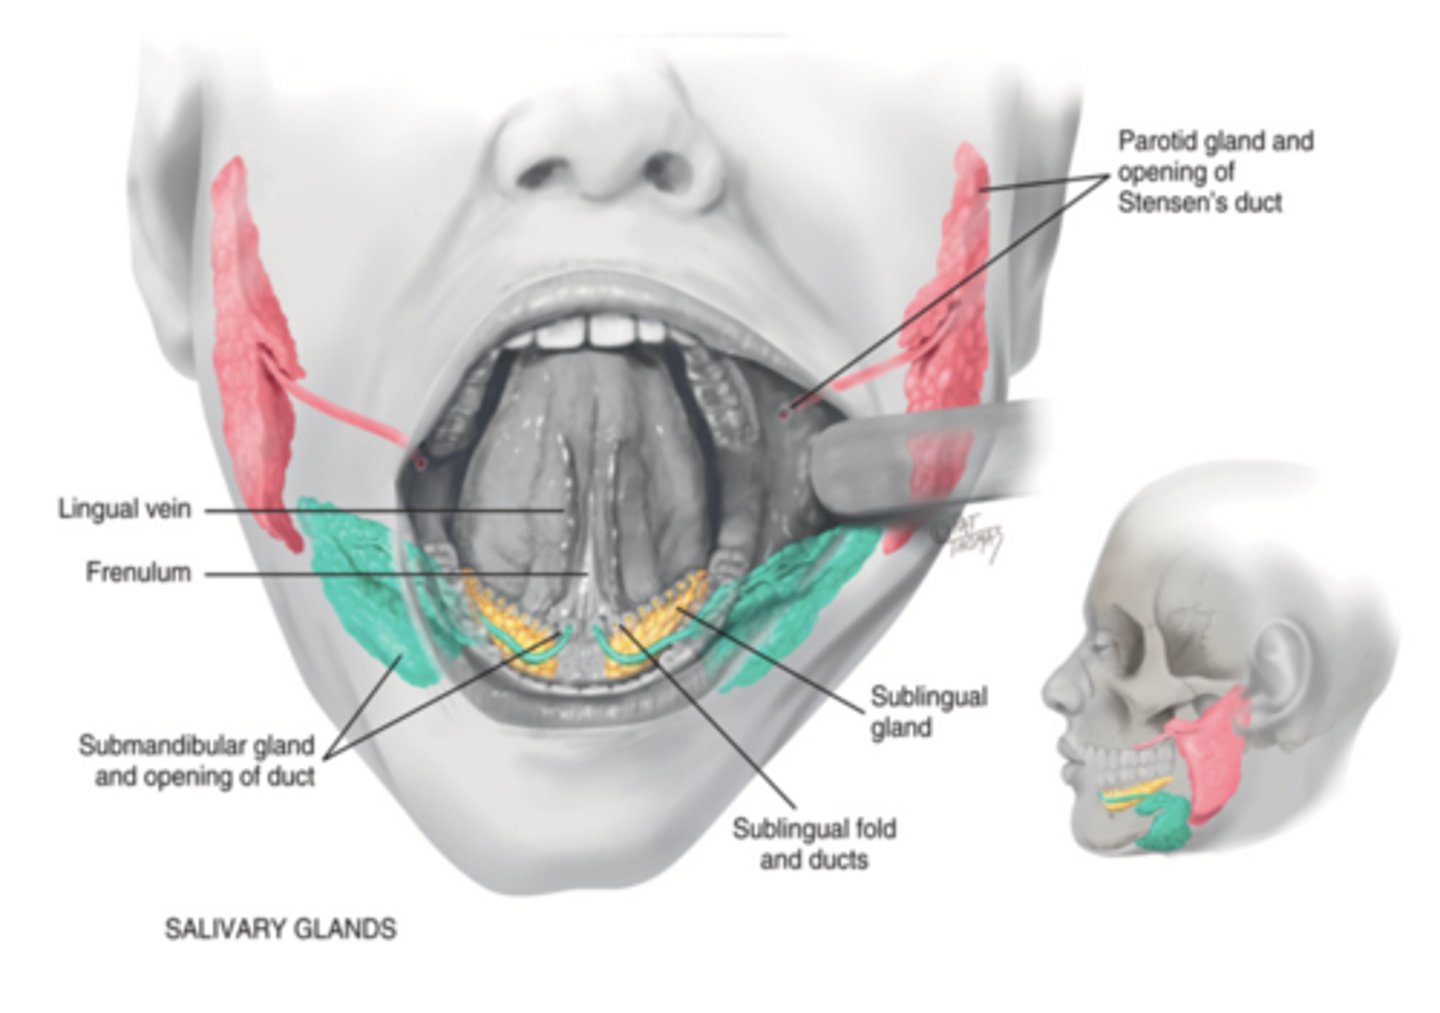

Salivary Glands

- Parotid

- Submandibular

- Sublingual

Parotid Gland

Salivary gland within the cheek, just anterior to the ear (red)

Submadibular Gland

Salivary gland under the mandible (green)

Sublingual Gland

Salivary gland under the tongue (yellow)